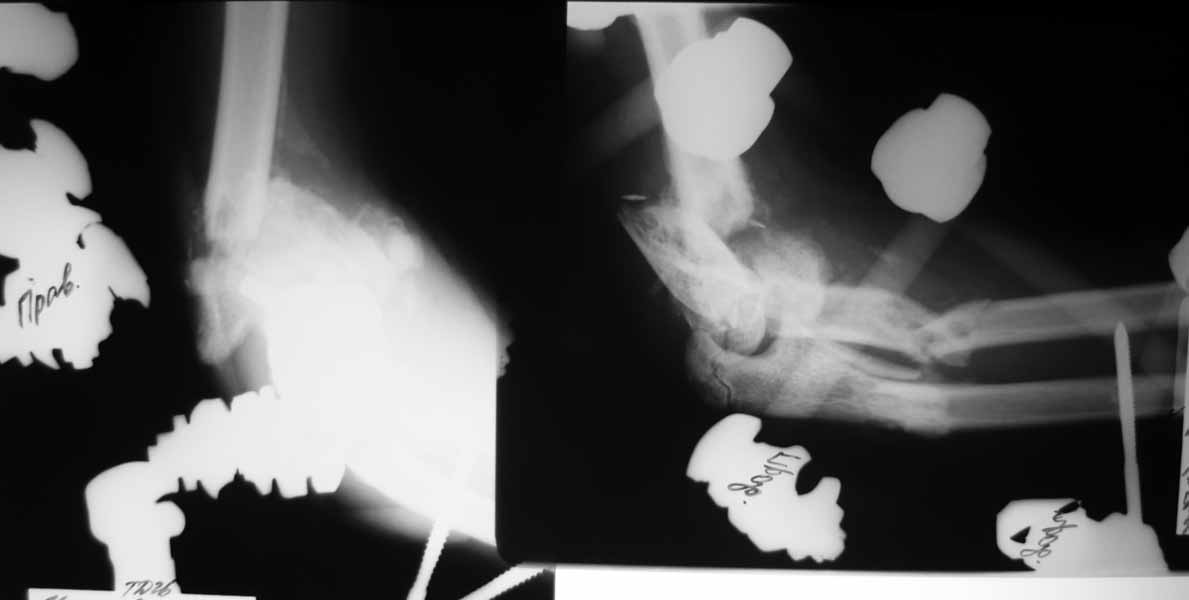

Re: тяжёлое повреждение локтевого сустава

Насколько оправдано снятие аппарата? В АВФ удобнее мыть, перевязывать, не так ли? Штанги графитовые и больших наводок при рКТГ не дадут. Выкладываю свежие рентгенограммы.

Согласен, при таком "качестве" снимков КТ необходимо. По поводу дистального метафиза - при благоприятном сопоставлении суставных опорных поверхностей - дефект заполнить не составит большого труда.

Мысли такие: на завтра сделаем некрэктомию участков локального сухого некроза кожи на локтевом суставе. Заживляем-первязываем. Лучевую кость есть желание синтезировать закрыто ESIN под ЭОП. Локтевую кость - открыто, как в пункте 4. Скорее всего - БИОС. Пункт 4 не вызывает никаких возражений. Смущает фраза первого оперирующего: что все отломки "вбиты в мышцы как при разделке мясником и обмотаны фасциями". При таком взаимоотношении с мягкими тканями сложно расчитывать на изящный выход из ситуации.